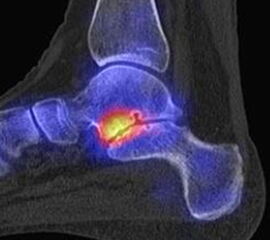

Abbildung 2.2.

Bilder eines Patienten mit Z. n. mehrfachen Sprunggelenksdistorsionen in der Vergangenheit, besonders heftige Distorsion des linken Sprunggelenkes 5 Wochen vor der Untersuchung. Die SPECT/CT zeigt eine instabile osteochondrale Läsion mit deutlicher Aktivierung.

Zum Lesen der Bildbeschreibung und zur Vollansicht bitte das Bild anklicken. Bild: H. C. Rischke